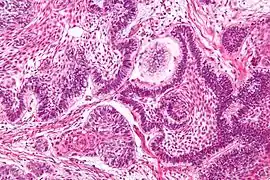

Micrograph of perivascular pseudorosettes

Micrograph of perivascular pseudorosettes Structure of a perivascular pseudorosette

Perivascular pseudorosette

A perivascular pseudorosette consists of a spoke-wheel arrangement of cells with tapered cellular processes radiates around a wall of a centrally placed vessel. The modifier “pseudo” differentiates this pattern from the Homer Wright and Flexner-Wintersteiner rosettes, perhaps because the central structure is not actually formed by the tumor itself, but instead represents a native, non-neoplastic element. Also, some early investigators argued about the definition of a central lumen, choosing “pseudo” to indicate that the hub was not a true lumen but contained structures. Nevertheless, this pattern remains extremely diagnostically useful and the modifier unnecessarily leads to confusion. Perivascular pseudorosettes are encountered in most ependymomas regardless of grade or variant. As such, they are significantly more sensitive for the diagnosis of ependymomas than true ependymal rosettes. Unfortunately, perivascular pseudorosettes are also less specific in that they are also encountered in medulloblastomas, PNETs, central neurocytomas, and less often in glioblastomas, and a rare pediatric tumor, monomorphous pilomyxoid astrocytomas.[2]